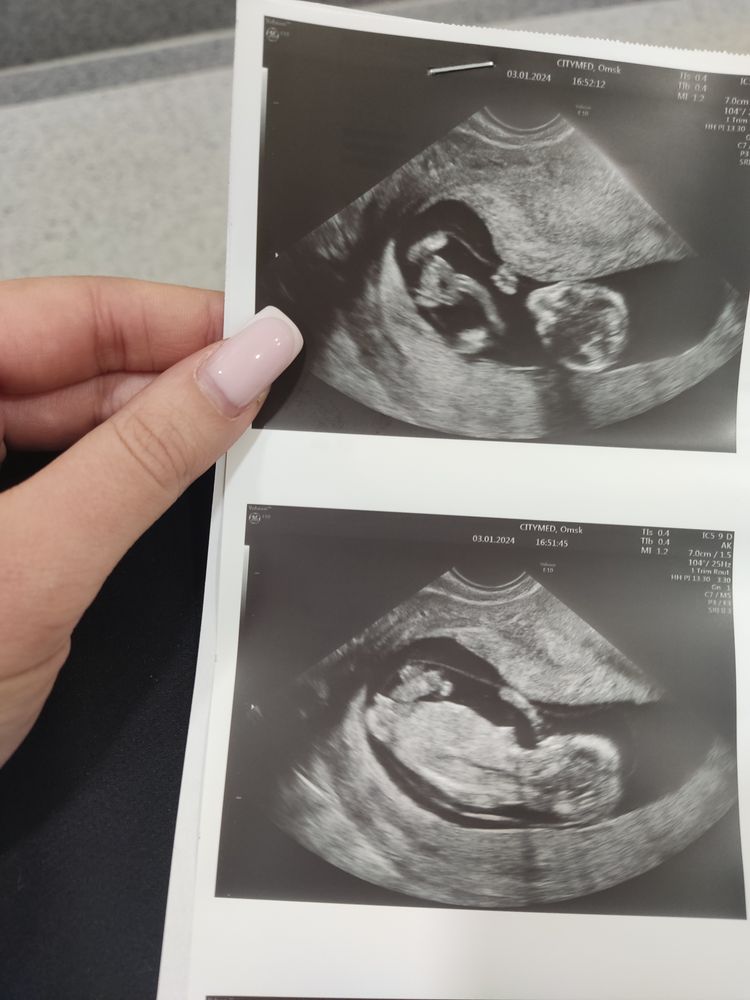

Валерия в Благополучная беременность 2 года Пол по УЗИ Затрудняюсь с категорией Кого видите? Мальчик или девочка? Посмотрите еще 20 записей на эту тему Отменить Ответить Леся Девочка 09.01.2024 Ответить Зара Похожа на девочку ) 06.01.2024 Ответить Маришка Девочка🥰 03.01.2024 Ответить Аннушка Это она. 🎀 03.01.2024 Ответить Юлия Мать Драконов 90% что девочка, половой бугорок прям лежит 03.01.2024 Ответить Анастасия С А разве в 12 недель можно точно определить? Врачи только предполагают, точно вам скажут на 2 скрининге. 03.01.2024 Ответить Nysha Анастасия С , нам сказалт в платной клинике 12.5 было, и всё точно. 08.01.2024 Ответить Валерия Nysha, сегодня был скрининг, 14 недель, сказали девочка 15.01.2024 Ответить Дарья Девочка 03.01.2024 Ответить Diana Девчонку вижу) 03.01.2024 Ответить Белка Девочка 03.01.2024 Ответить Blue Berry По последнему фото похоже на девочку 03.01.2024 Ответить Поход в баню Пожалуйста подскажите Чаты Беременных Выберите чат: Январята-2026 Февралята-2026 Мартята-2026 Апрелята-2026 Майчата-2026 Июнята-2026 Июлята-2026 Августята-2026